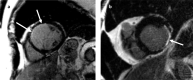

Cardiovascular imaging has significantly evolved since the turn of the century. Progress in the last two decades has been marked by advances in every modality used to image the heart, including echocardiography, cardiac magnetic resonance, cardiac CT and nuclear cardiology. There has also been a dramatic increase in hybrid and fusion modalities that leverage the unique capabilities of two imaging techniques simultaneously, as well as the incorporation of artificial intelligence and machine learning into the clinical workflow. These advances in non-invasive cardiac imaging have guided patient management and improved clinical outcomes. The technological developments of the past 20 years have also given rise to new imaging subspecialities and increased the demand for dedicated cardiac imagers who are cross-trained in multiple modalities. This state-of-the-art review summarizes the evolution of multimodality cardiac imaging in the 21st century and highlights opportunities for future innovation.